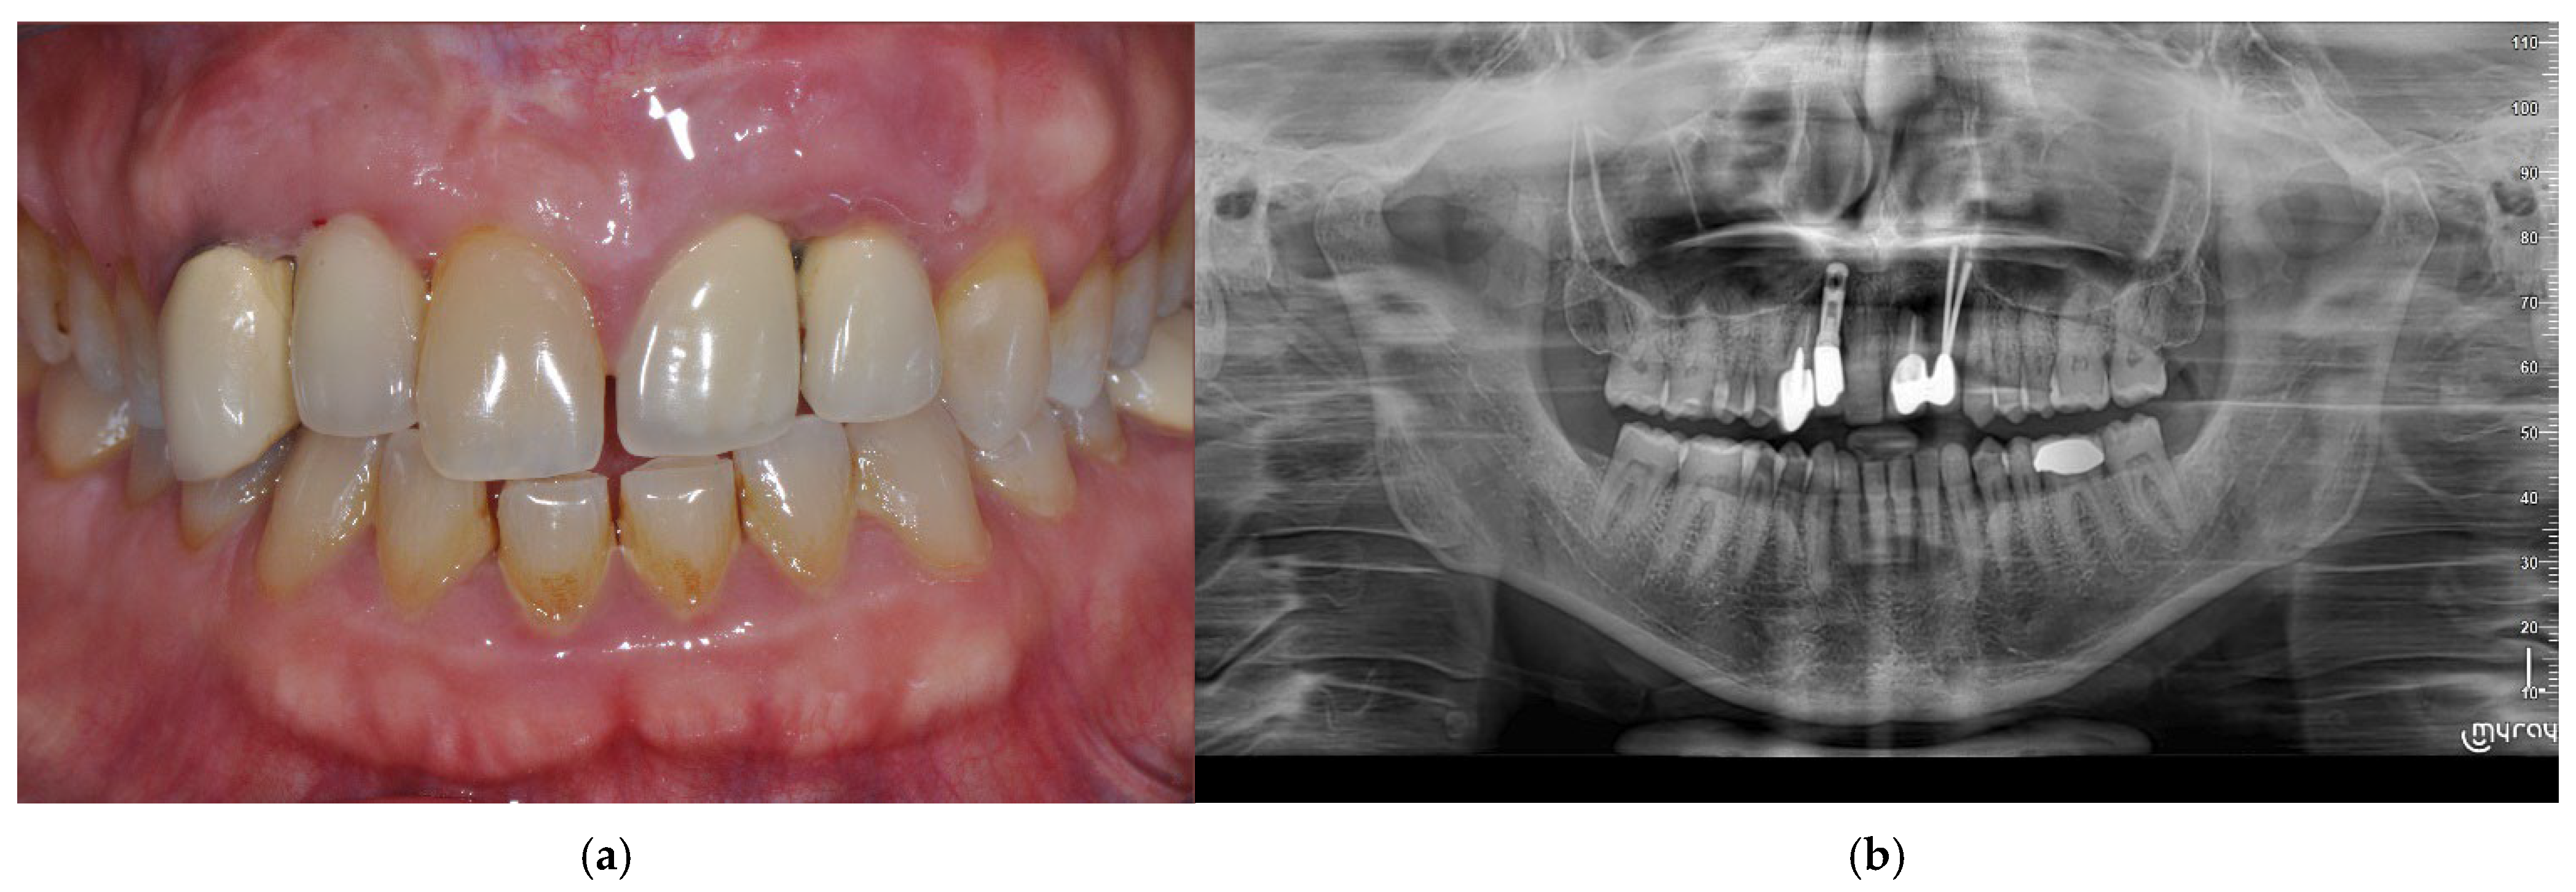

2.1. Case Presentation

2.2. Surgical Procedure